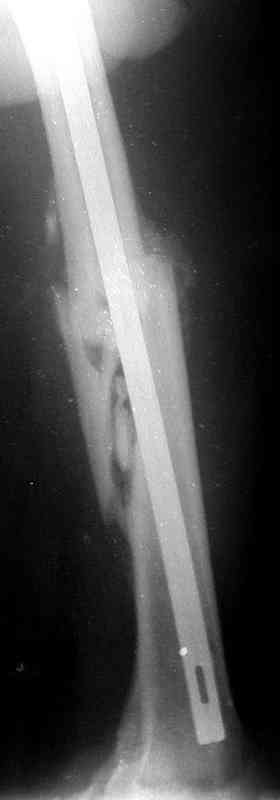

месяцев дистракции укорочение левого бедра удалось полностью устранить. 22.02.00, т.е. через 2 месяца после повторного остеосинтеза, больному произведено дистальное блокирование штифта двумя винтами и демонтирован аппарат Илизарова. В течение 2 недель после операции больной ходил с помощью костылей, потом 2 недели с тростью. Опороспособность и функция оперированной конечности полностью восстановились через 4 недели после операции.

Фиксаторы удалены через 12 месяцев после операции, выполненной по поводу замедленной консолидации перелома бедра с его укорочением.

На финальных снимках видно - сращение прям таки железное. Если Вы не устали отвечать, осмелюсь задать еще вопрос - что-то принимал пациент в целях ускорения сроста (кальций, режим питания). Интересны также вопросы восстановления функций конечности - в какой период были рекомендованы группы упражнений для восстановления основных групп мышц?